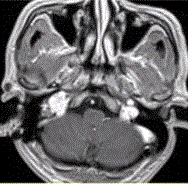

问题 患者男,54岁,右侧耳部不适,耳镜检查示蓝色鼓膜。HRCT显示如下图。 可能的诊断为

选项 A.颈静脉球瘤 B.颈静脉孔区神经鞘瘤 C.颈静脉孔区脑膜瘤 D.中耳乳突炎 E.中耳胆脂瘤

答案 A